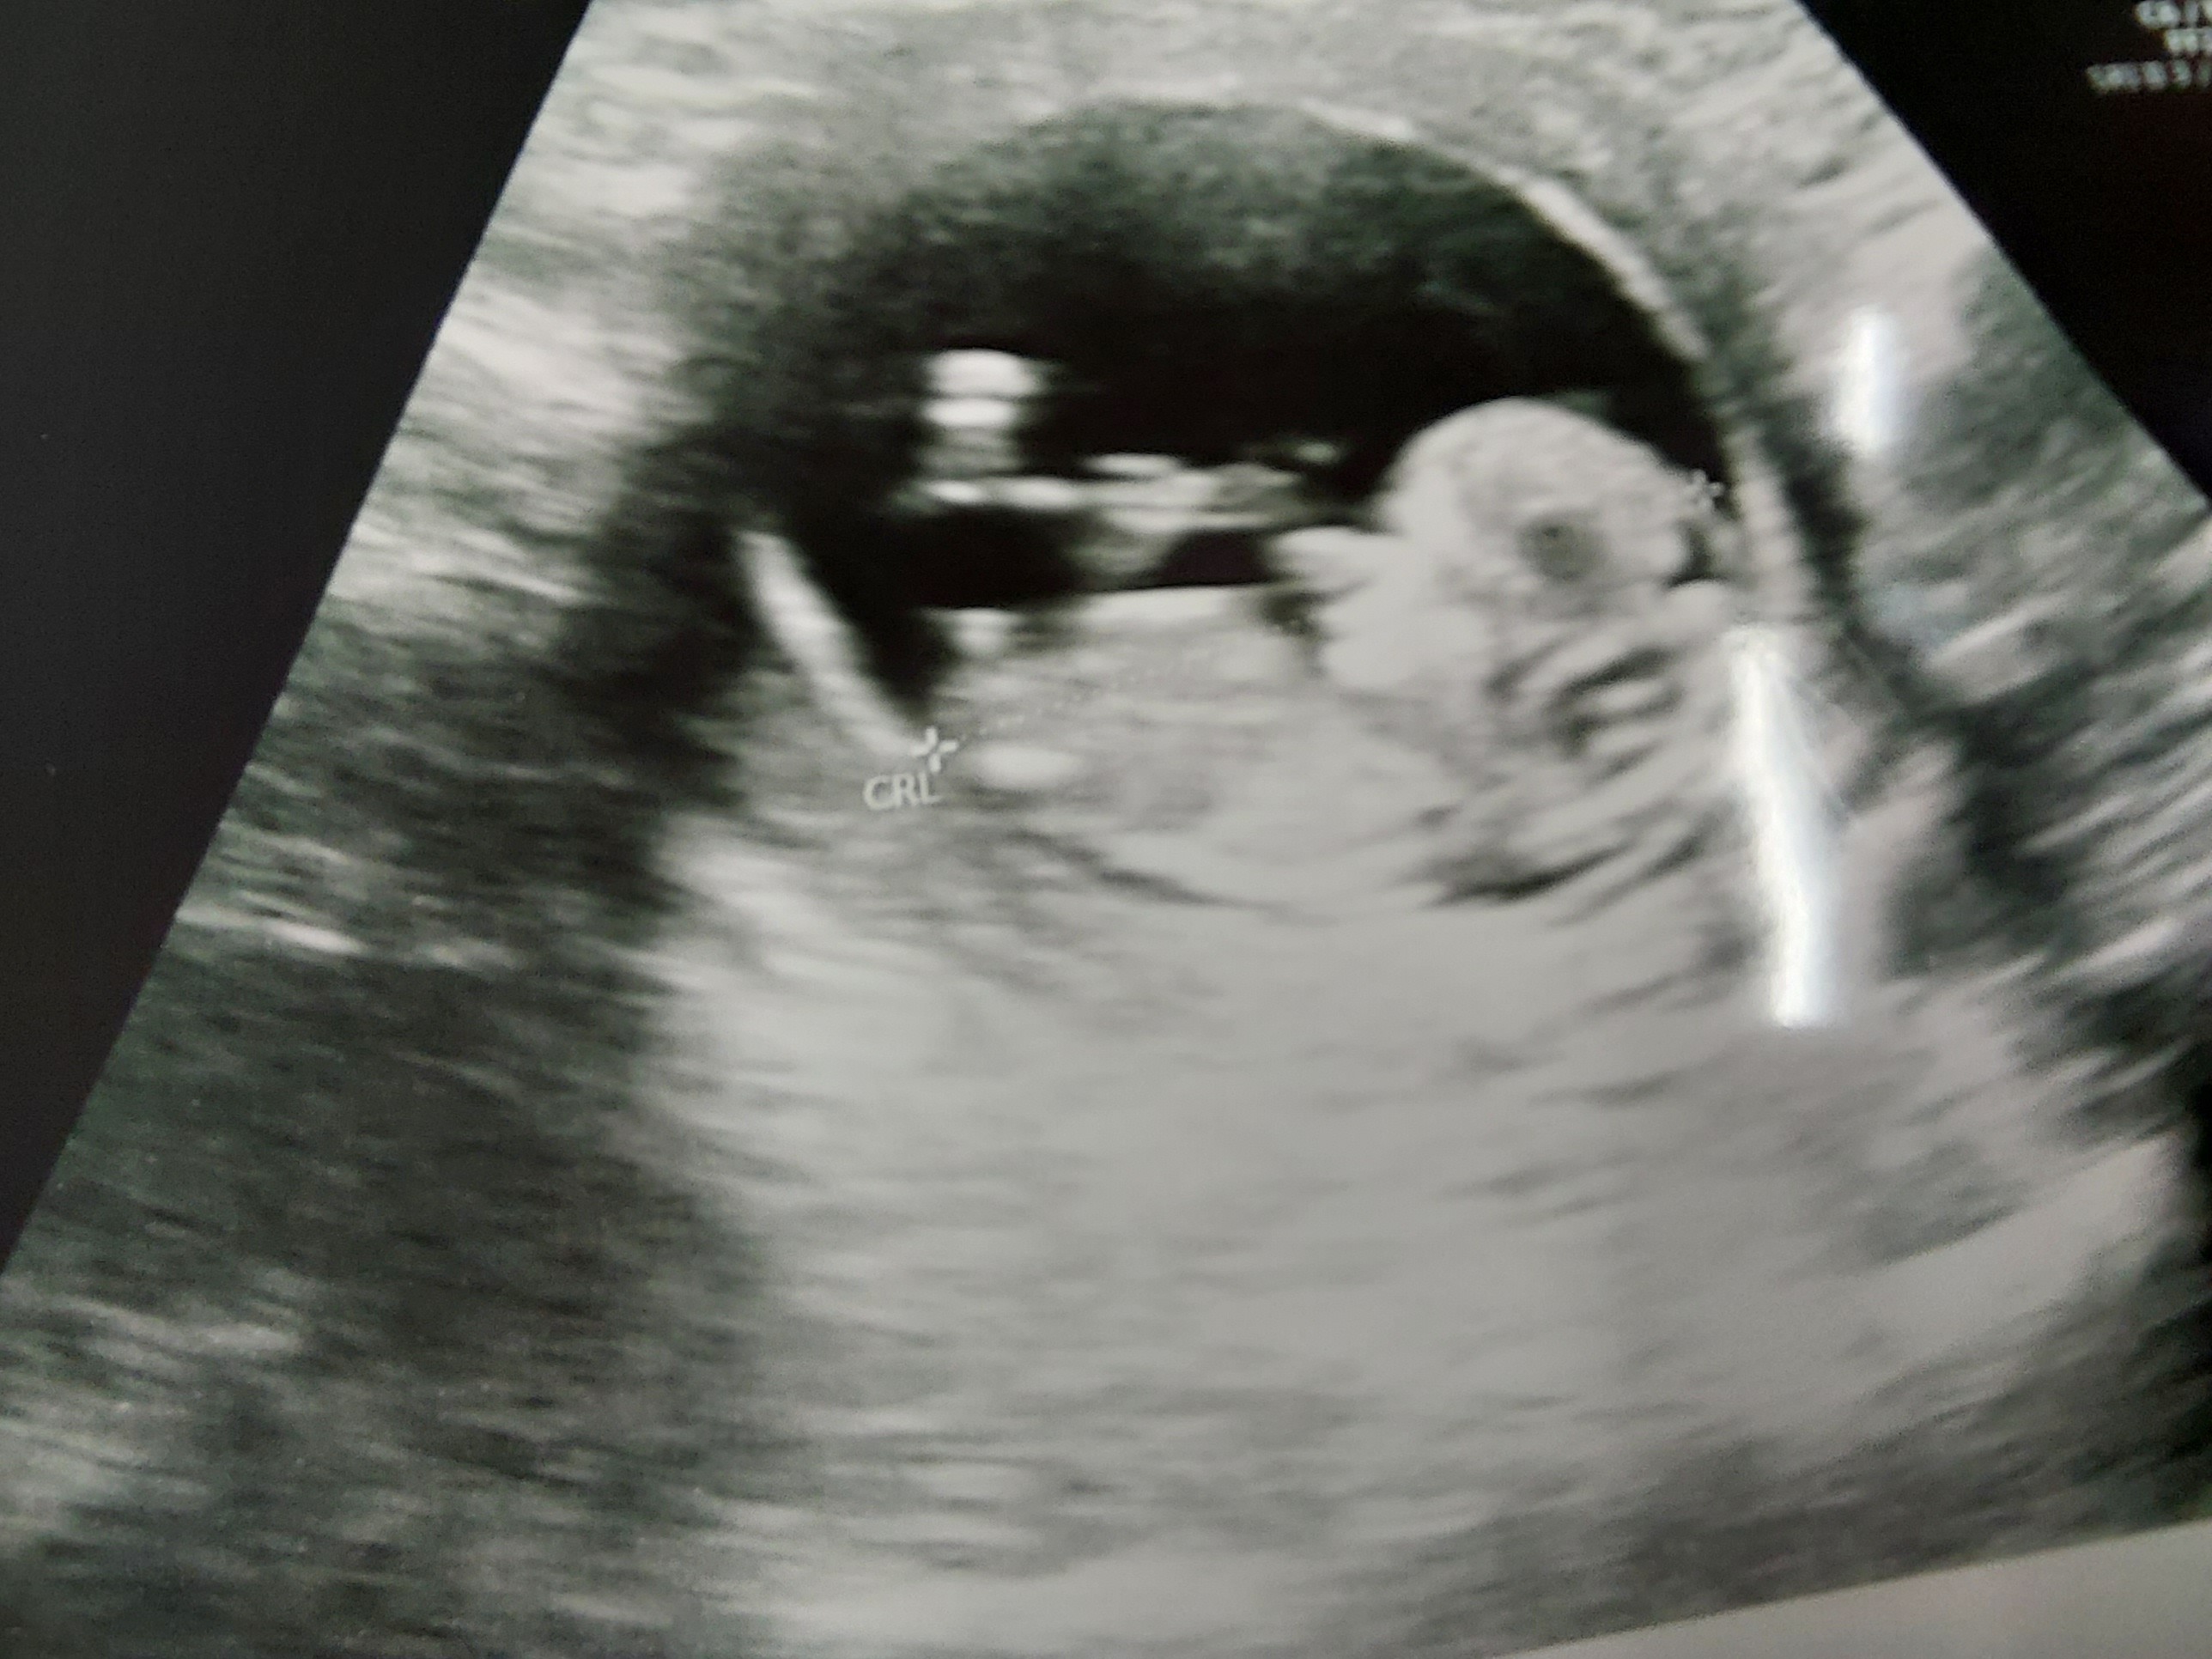

Potem w lux med miałam USG prenatalne. Nie spodziewałam się tu jakiś cudów ale kość nosową obecna. NT 1.2 - poza tym wszystko tak jak trzeba. Łożysko mam na tylnej ścianie więc niby po tym cc lepiej. Lekarz nie mówił nic o płci, ale wiecie ja jestem na tych różnych grupach i chyba jednak słabo nam wyszła afirmacja bo dla mnie to chłopiec 🤡